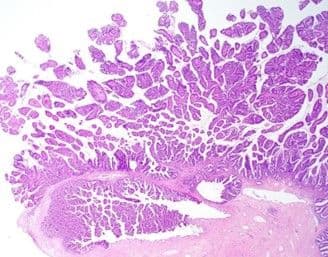

IMRT uses a multifield beam arrangement with variable beam fluence in order to confirm to radiation targets. This technique balances need to deliver high target coverage by the prescription dose while minimizing dose exposure to surrounding organs [178, 179]. Planning is performed primarily using CT, augmented with MRI and PET overlays. In planning, dose-volume histograms are used to plot the proportion of target volume or organ-at-risk volume in order to define the dose over the course of the radiation prescription (Figure 16).

Figure 16. Dosimetry planning using IMRT with the goal of delivering 5040cGy to the primary cervical lesion (a) as well as a right enlarged lymph node (b) while minimizing toxicity to small bowel (outlined in red along the anterior abdomen).

Studies have demonstrated comparable clinical outcome with lower gastrointestinal and bone marrow toxicity using IMRT compared to whole pelvic radiation [180, 181]. RTOG 1203 (TIME-C) was a phase III randomized controlled trial comparing 3-dimensional radiation versus IMRT in the postoperative treatment of patients with cervical and endometrial cancer and showed improved patient-reported short-term gastrointestinal and urinary outcomes with IMRT [182]. However, there is no data that IMRT improves disease specific survival or overall survival compared to conventional whole pelvic techniques. Furthermore, volumes may be sensitive to respiration, bladder fill, and rectal fill [183].